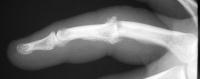

This young man had been treated for a rotating blade injury of the ring finger proximal interphalangeal joint. He had gross instability, pain and stiffness. These radiographs are before and after proximal interphalangeal joint reconstruction with the Avanta proximal interphalangeal joint surface replacement implant arthroplasty.

Lateral view: